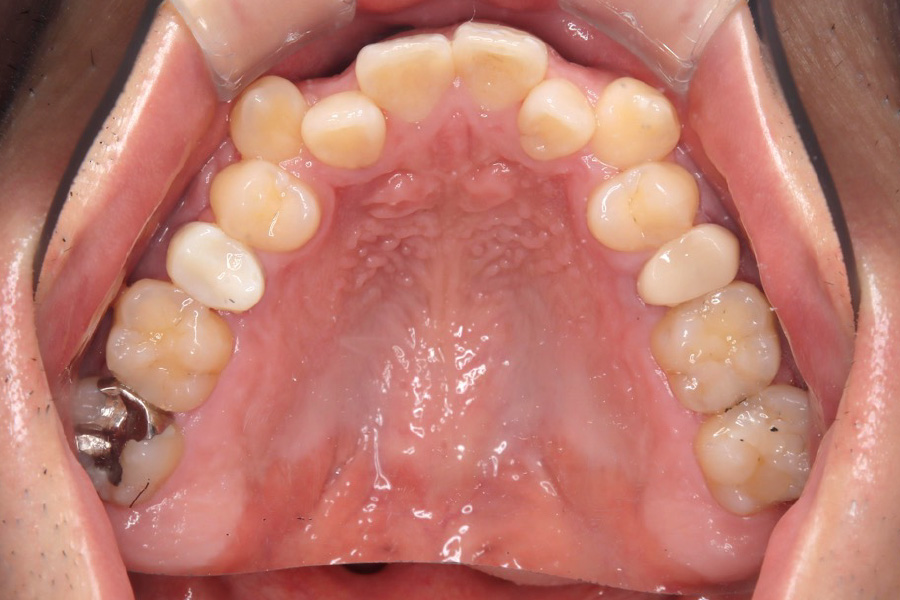

治療後

主訴 歯のガタつき

期間 2年

治療内容 インビザライン矯正

非抜歯

治療に伴うリスク 矯正終了後は、リテーナーを指示通りに使用し、歯の後戻りを防ぐ必要があります。